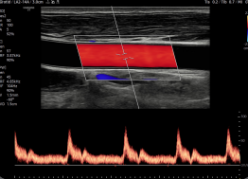

ArterialAnalysis™ y AutoIMT+™